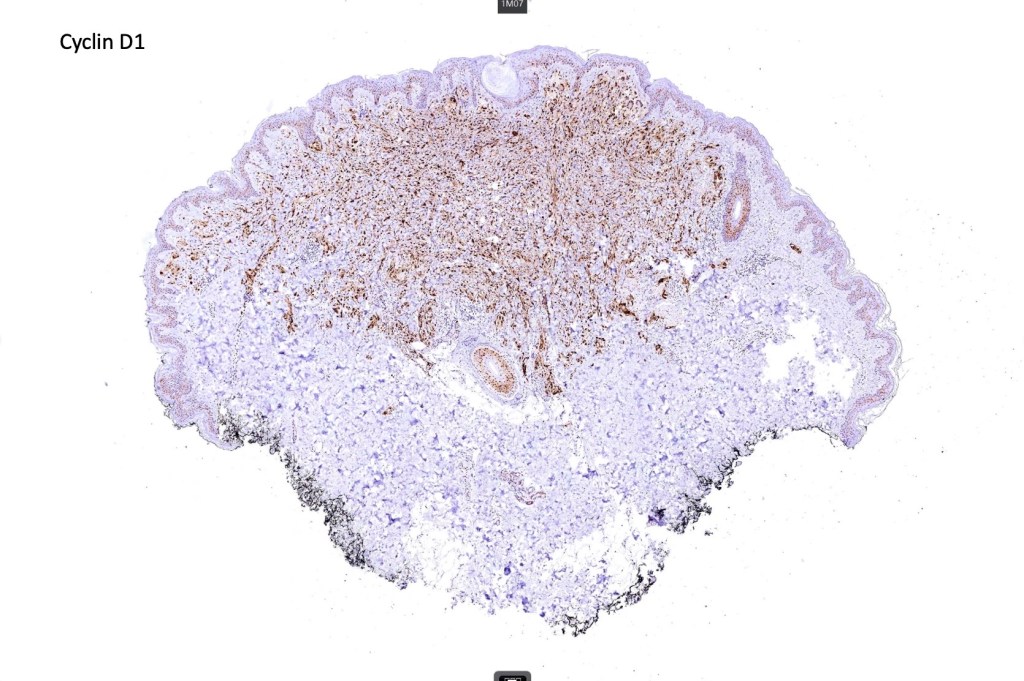

•Strong nuclear & cytoplasmic expression of β catenin, cyclin D1 & LEF1

•WNT pathway activated usually through gain of function mutations of CTNNB1